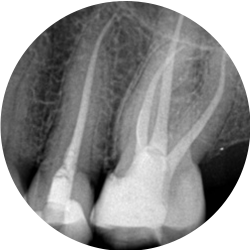

Your first appointment will generally be a consultation where a throrough examination of your presenting problem will be carried out to diagnose orofacial pain, pulpal injury and to determine if the tooth in question is a good candidate for endodontic therapy.

A careful assessment will be made of your tooth to see if retreatment is the best option for you. Sometimes teeth have other more significant problems that may have a significant impact on the success of the retreatment and in these cases the tooth may have to be removed.

Occasionally, a nonsurgical root canal procedure alone cannot save your tooth and your endodontist will recommend surgery.

There are many surgical procedures that can be performed to save a tooth. The most common is called an apicoectomy, or root-end resection, which is occasionally needed when inflammation or infection persists in the bony area around the end of your tooth after a root canal procedure. In this microsurgical procedure, the endodontist opens the gum tissue near the tooth to see the underlying bone and to remove any inflamed or infected tissue. The very end of the root is also removed. A small filling may be placed to seal the end of the root canal and few stitches or sutures are placed to help the tissue heal. Over a period of months, the bone heals around the end of the root. Local anesthetics make the procedure comfortable, and most patients return to their normal activities the next day. Postsurgical discomfort is generally mild.